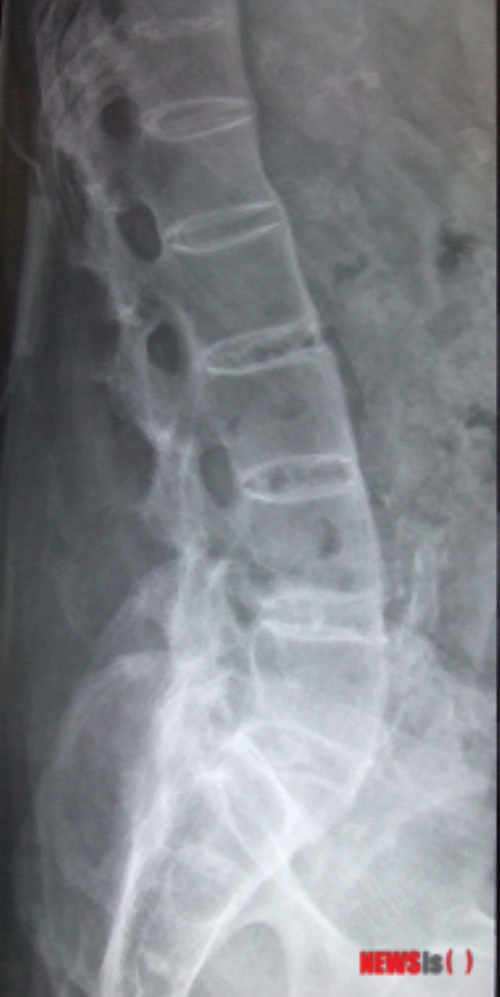

[½ÃÅ©´º½º À̺¸¶ó ÀÎÅϱâÀÚ] ÃÖ±Ù ½º¸¶Æ®Æù »ç¿ëÀÌ Å©°Ô ´Ã¾î³ª¸é¼­ 20~30´ë ¸ñµð½ºÅ© ȯÀÚ°¡ ±ÞÁõÇϰí ÀÖ´Ù.

ÇÑ Àü¹®º´¿ø¿¡¼­ Áö³­ÇØ ¸ñ µð½ºÅ© Áø´ÜÀ» ¹ÞÀº ȯÀÚ 8958¸íÀ» 2011³âµµ ȯÀÚ(2940¸í)¿Í ºñ±³ÇÑ °á°ú, 20~30´ë ºñÁßÀÌ 17.6%¿¡¼­ 3³â »õ 30.3%·Î µÎ ¹è °¡±îÀÌ Áõ°¡ÇÑ °ÍÀ¸·Î Á¶»çµÆ´Ù. ¹Ý¸é ȯÀÚ ºñÁßÀÌ ³ô¾Ò´ø 50~60´ë´Â °°Àº ±â°£ 54.2%¿¡¼­ 38.7%·Î ÁÙ¾ú´Ù.

¿¬·É´ëº° ȯÀÚ¼ö·Î ºñ±³Çغ¸¸é 20´ë ȯÀÚ°¡ 109¸í¿¡¼­ 856¸íÀ¸·Î 7.9¹è ´Ã¾ú°í, 30´ë´Â 407¸í¿¡¼­ 1850¸íÀ¸·Î 4.6¹è Áõ°¡ÇÑ °ÍÀ¸·Î ³ªÅ¸³µ´Ù. ÀÇ·áÁøÀº 20~30´ë ¸ñ µð½ºÅ© ȯÀÚ°¡ Å« ÆøÀ¸·Î Áõ°¡ÇÑ ¿øÀÎÀ¸·Î ÀþÀº ÃþÀÇ À߸øµÈ ÀÚ¼¼¿Í »ýȰ½À°üÀ» ²Å¾Ò´Ù. ÀÌ °¡¿îµ¥¼­µµ ½º¸¶Æ®Æù, PC »ç¿ë ½Ã°£°ú ¹«°üÇÏÁö ¾Ê´Ù´Â °Ô ÀÇ·áÁøÀÇ ¼³¸íÀÌ´Ù.